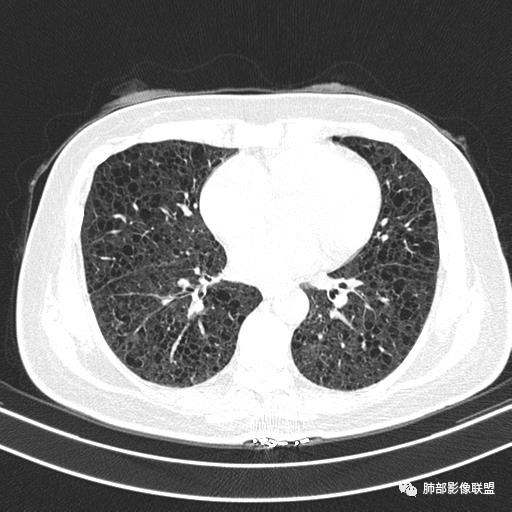

双肺弥漫囊腔,累及肋膈角,囊腔形态相对规则单一。

CT平扫示双肺弥漫分布大小不等囊状薄壁透光区,无内、中、外带分布差异,间质稍示增厚。拟LAM

中年女性育龄期妇女,咳嗽气喘,无吸烟史,有苯吸入史。影像:双肺弥漫均匀小囊腔,无明显分布优势,囊腔形态欠规则,壁薄,部分囊腔边缘血管征,伴双肺弥漫磨玻璃影,无结节,考虑lam,鉴别苯中毒肺损伤,囊腔多有分布优势,小叶中心分布为主,形态规整等

女,46,活动性气喘1年。苯吸入史半年。胸部CT:两肺弥漫囊腔,上至肺尖,下至肋膈角,形态类似小囊腔。考虑:LAM,鉴别LIP,BHD,PLCH等。

双肺弥漫大小不一薄壁含气囊腔,囊间肺组织正常,正常肺背景,肺尖肺底受累;青年女性,气喘,支持LAM

双肺多发大小相近的囊状影,分布趋势趋于一致,中年女性,考虑LAM。部分囊内见血管及分隔影,小叶中心性肺气肿代排

CT表现:双肺弥漫大小不等的薄壁囊腔,囊壁<2mm,外形规则,血管影多位于囊腔周围,囊腔之间肺组织正常,随着疾病进展到晚期,囊腔变大、增多,不可胜数,囊腔可融合成较大的囊,与肺气肿相似,形成间质性肺纤维化。部分病例可出现结节影。